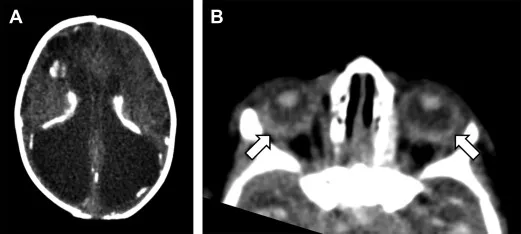

- Congenital (📌 Sabin's Triad): Chorioretinitis (most common), hydrocephalus, intracranial calcifications.

⭐ Reactivation in AIDS (CD4 < 100) causes multiple ring-enhancing brain lesions.

- Causes cysticercosis; Neurocysticercosis (NCC) is a major cause of seizures.

- Dx: CT/MRI (ring-enhancing lesions, scolex), EITB. Rx: Albendazole + steroids for viable cysts.

⭐ > Neurocysticercosis is the most common preventable cause of epilepsy in the developing world.